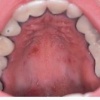

Glossitis rhomboidea mediana

– Keele keskosa arengus osalev tuberculum impar võib keele keskjoonel jääda nähtavaks punetava, sileda ja rombitaolise kõrgendiku või lohuna. – Muutus on ohutu, kuid seda tuleb eristada keele kasvajatest (vähegi...